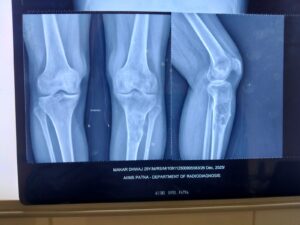

When he presented at AIIMS Patna on May 13, 2025, doctors identified a pathological fracture of the tibia, raising suspicion of an underlying malignancy. Subsequent investigations confirmed Ewing Sarcoma, a rare and highly aggressive bone cancer that often necessitates amputation.

On March 13, 2026, a highly specialized limb salvage surgery was performed. The cancer affected segment of the tibia was carefully removed along with surrounding tissue. In a cutting edge approach the excised bone was treated with high dose extracorporeal radiation (50 Gy) to eradicate residual cancer cells. The sterilized bone was then re-implanted into the patient’s leg. Structural stability was restored using titanium plates and screws and a muscle flap reconstruction was performed to enhance healing and functionality.